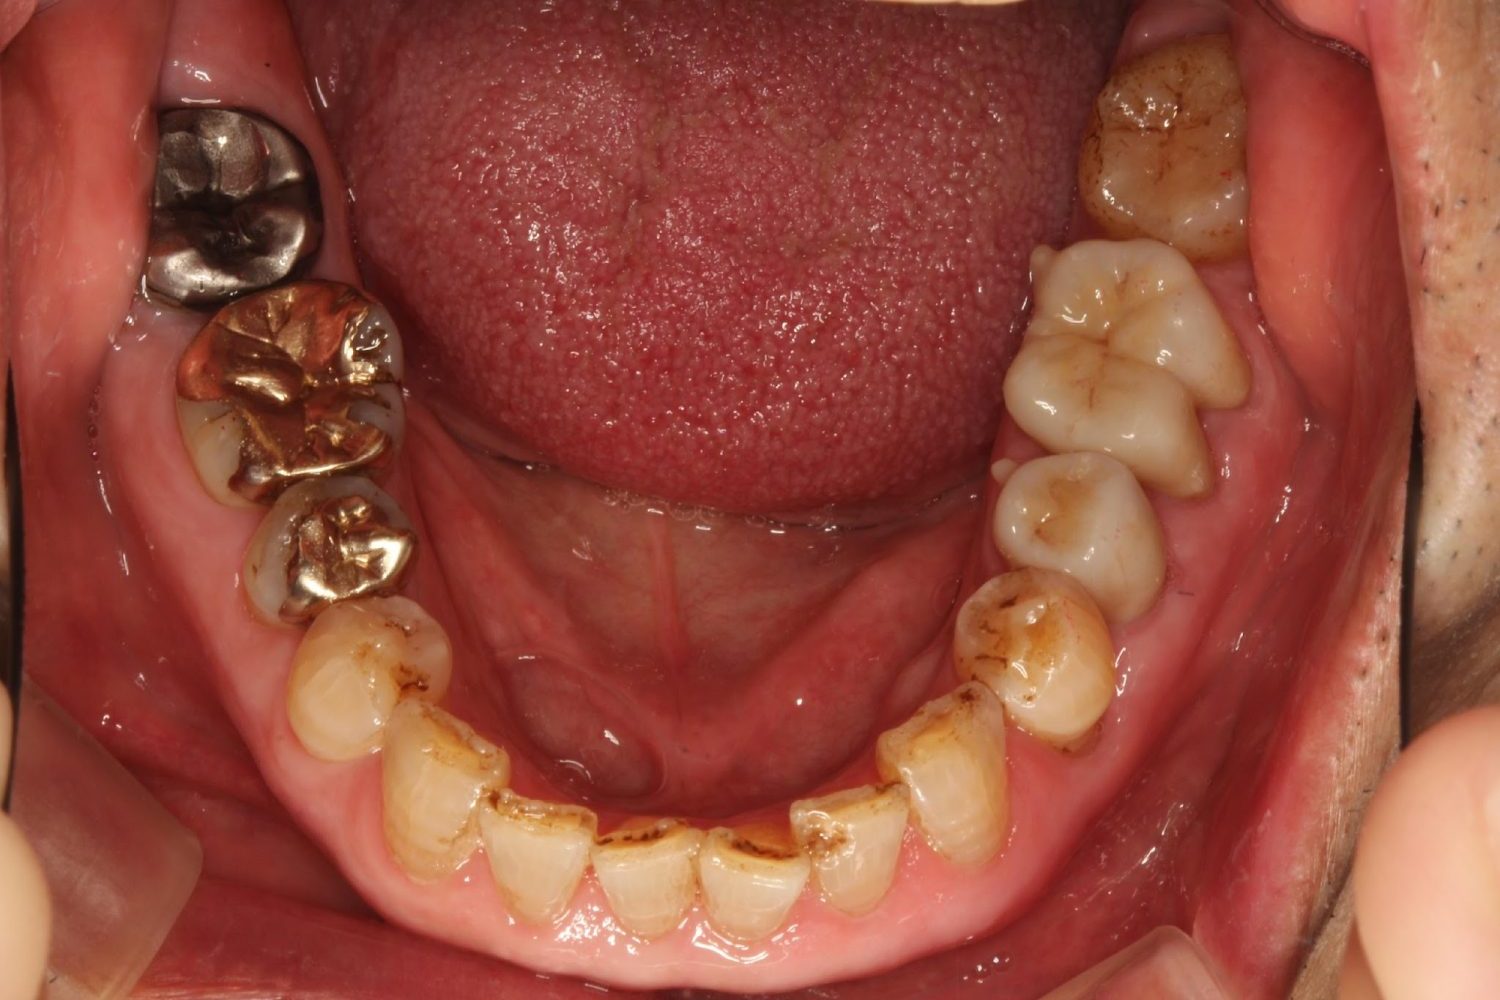

インプラント治療の症例紹介③

Before

After

主訴

むし歯の治療

治療内容

保存不可能な歯の抜歯

下顎にインプラント埋入し咬合再構成

治療費

2,688,400円(税込)

治療期間

14か月

治療回数

21回

想定されたリスク

※上部構造の形態が複雑になるため清掃が難しくなる。インプラント周囲炎の恐れがありました。

多数歯う蝕および多数歯欠損による咬合崩壊、保存不可能な歯の抜歯により上下無歯顎に。下顎に6本インプラント埋入する事で咬合再構成を行った。